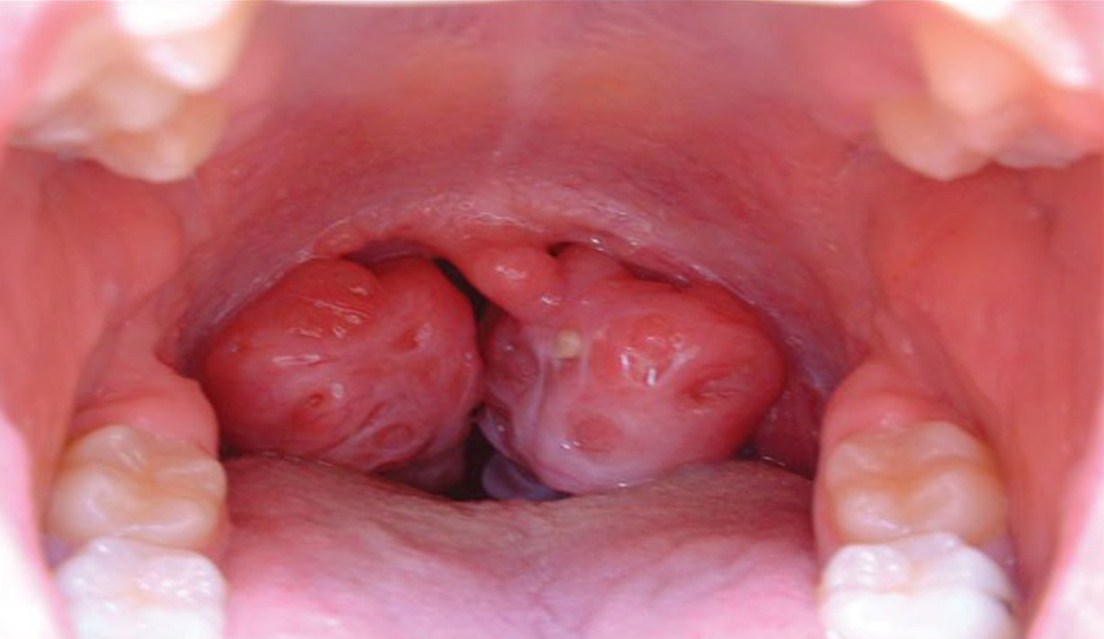

Kondisi amandel ini sangatlah umum dirasakan oleh orang dengan berbeda penyebab. Namun penyebab umumnya timbul karena serangan atau infeksi dari berbagai jenis virus tertentu. Langkah utama utama untuk mengatasi kondisi tersebut adalah dengan mencegah beberapa penyebabnya seperti mulai dari makanan, minuman hingga kebersihan tubuh sekitar. Banyak orang yang berpendapat bahwa penyembuhan amandel ini harus melalui langkah medis dari operasi. Tapi, sebenarnya ada langkah jitu yang terbukti dapat menyembuhkan amandel dengan cepat tanpa kambuh kembali.

Jika langkah operasi di ambil, maka kemungkinan besar resiko efek samping pun akan berimbas pada kesehatan tubuh anda. Maka dari itu, lebih pintar-pintar lagi memilih jenis penanganan dalam mengatasi amandel dengan cepat dan tepat.